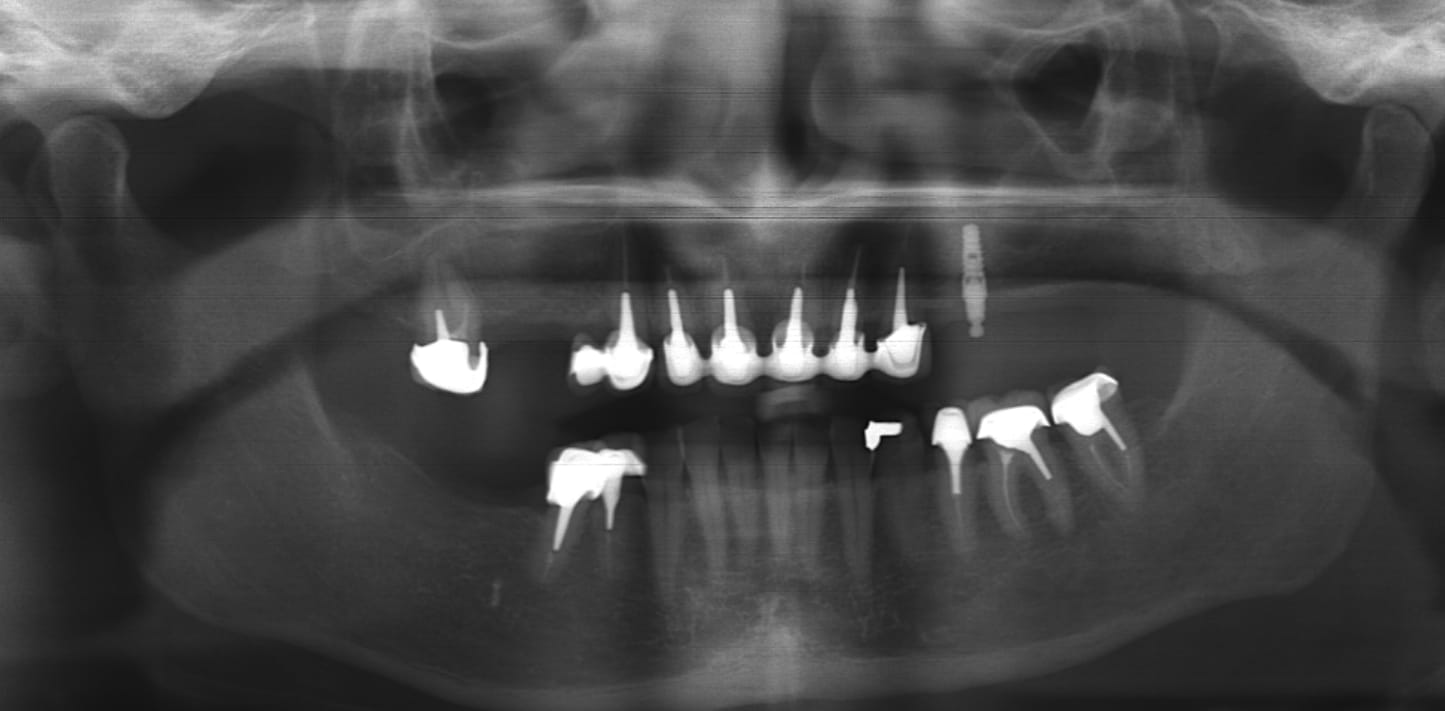

J'ai une patiente qui vient avec comme désiderata la suppression d'une petite PAP secteur 2 qui est maintenue par un attachement boule sur implant.

Elle ne connait pas la marque de cet implant, posé il y a 8 ans, qui est parfois douloureux à cause d'une petite mucosite et d'une legère perte osseuse.

Je lui ai proposé la réalisation d'un bridge sur implant 24-26 avec dépose de cet implant.

En effet, ni la position ni l'angulation ne me convienne.

Je suis un peu réticent a déposer cet implant qui n'est pas en si mauvais état, mais prothétiquement ca ne le fera pas trop.

Je déposerais l’implant (Euroteknika Natura?) sans hésiter avec comblement puis poserais 3 implants pour 4 dents

C'est bien un naturall euroteknika en tout cas